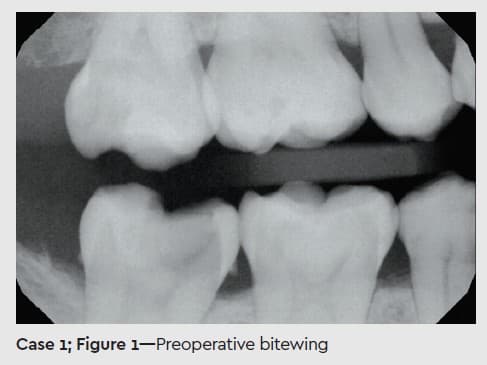

In this first case, my patient was a 37-year-old woman with no revealed or evident health problems or history beyond a lifetime of poor diet choices. Gross decay was present at her initial visit on 19 of 28 teeth, but all appeared restorable (Figures 1 and 2).